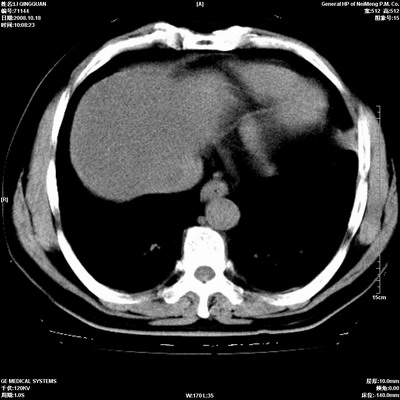

以下是引用duguo在2008-10-19 13:59:00的发言:[br]左肺上叶支气管狭窄,首先考虑中心型肺癌伴阻塞性肺炎\\肺不张.

以下是引用ybing在2008-10-19 12:58:00的发言:[br]左肺上叶阻塞性炎症-建议支气管镜进一步检查除外中央型肺癌

以下是引用随光逐影在2008-10-19 14:31:00的发言:[br]考虑左肺中央型肺癌并左肺上叶阻塞性肺炎,肺不张。